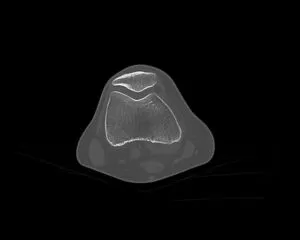

CT

GE社製Revolution ACT(16列)を導入しています。X線を利用して体の断面(輪切り)を撮像する検査です。この輪切りの画像をコンピューターで処理することにより、様々な方向からの断面像や3D画像を得ることができます。

CTで検査した画像